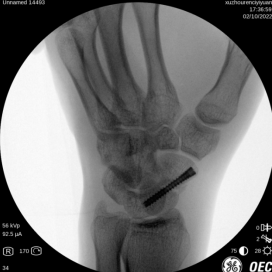

爱运动的小刘在和朋友打球时不慎与队友相撞摔倒,摔倒时他左手手掌惯性撑地,导致左腕疼痛剧烈,无法进行正常活动。手外科唐医生接诊后通过X片及三维重建均显示小刘为左腕舟状骨骨折。

术前X片(左图)术前三维重建(右图)

术中摄片

唐医生使用天玑骨科机器人辅助手术,精准定位,避免反复穿刺导致的二次损伤,大大缩短手术时间,术后促进骨质愈合,仅手腕处一个钉眼大小的伤口。

术后照片